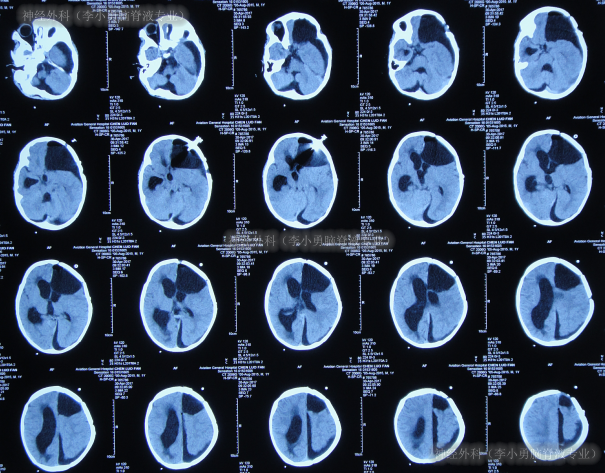

但出院后仅半月时间内,出现了不断加重的左侧肢体轻瘫,口角右斜,头向左斜和走路不稳的症状,出院后18天即2017年4月24日,当地医院查头颅CT硬膜下积液、脑积水加重(图-6)。

图-6:2017年4月24日头颅CT

入院后4天即2017年4月28日,进行了第1次手术:硬膜下积液引流术。术后3天即2017年4月30日,查头颅CT示硬膜下积液引流术后,脑室有所缩小(图-7)。

图-7:2017年4月30日头颅CT

硬膜下积液引流术后6天即2017年5月3日,患者症状仍未改善,查头颅核磁(图-8)后脑积水反而变更多,认为有“囊肿”。

图-8:2017年5月3日头颅核磁增强

第2次手术:软性神经内镜脑室内检查术和脑内囊肿造瘘术后第2天(2017年5月6日)和第3天(2017年5月7日)两次查头颅CT(图-9)均示脑室仍未缩小,反进一步扩张。

图-9:2次查头颅CT

第2次手术软性神经内镜脑室内检查术和脑内囊肿造瘘术后10天即2017年5月14日,进行了第3次手术:脑室腹壁外引流术;术后当天查头颅CT后认为脑室有缩小(图-10)。

图-10:2017年5月14日头颅CT

第3次手术脑室腹壁外引流术19天即2017年6月2日,查头颅CT较2017年5月14日示未见脑室缩小(图-11)。

图-11:2017年6月2日头颅CT

第3次手术脑室腹壁外引流术37天即2017年6月20日,查头颅CT(图-12)后计划明天进行脑室腹腔分流术。

图-12:2017年6月20日头颅CT

第4次手术脑室腹腔分流术后3天即2017年6月23日,查头颅CT示脑室仍扩张(图-13)。

图-13:2017年6月23日头颅CT

第4次手术脑室腹腔分流术后20天即2017年7月10日,查头颅CT示脑室再次扩张更大(图-14)。

图-14:2017年7月10日头颅CT